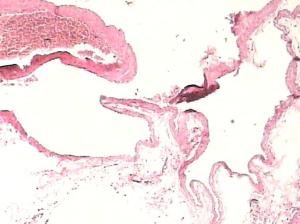

2.病理大體標本可見到病變為單發或多發,呈暗紅色圓形或卵圓形,稍隆起與周圍灰紅色黏膜分界尚清,多有淺表性潰瘍糜爛,有呈假息肉改變;有的呈多灶性,節段性分布或成片分布。顯微鏡下可見到胃腸黏膜下層的畸形動脈增粗、增多、彎曲,但無動脈瘤樣改變。伴隨靜脈明顯擴張,充血,血管壁稍厚。HE染色畸形血管在組織學上並無異常改變,血管的內外膜及肌層均完好無損病理檢查也無血管炎症或血管硬化的證據。網狀纖維及彈力纖維染色,畸形動脈之彈力組織亦完好無損。血管橫徑為1.44~10.89mm,平均為3.46±2.03mm。